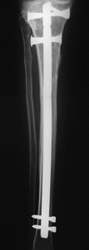

Tibiakopffraktur mit Tibiaschaftfraktur. Geschlossene Nagelung. Nach 3 Wochen volle Belastung. Die rechten zwei Röntgenbilder zeigen den Befund nach einem Jahr.